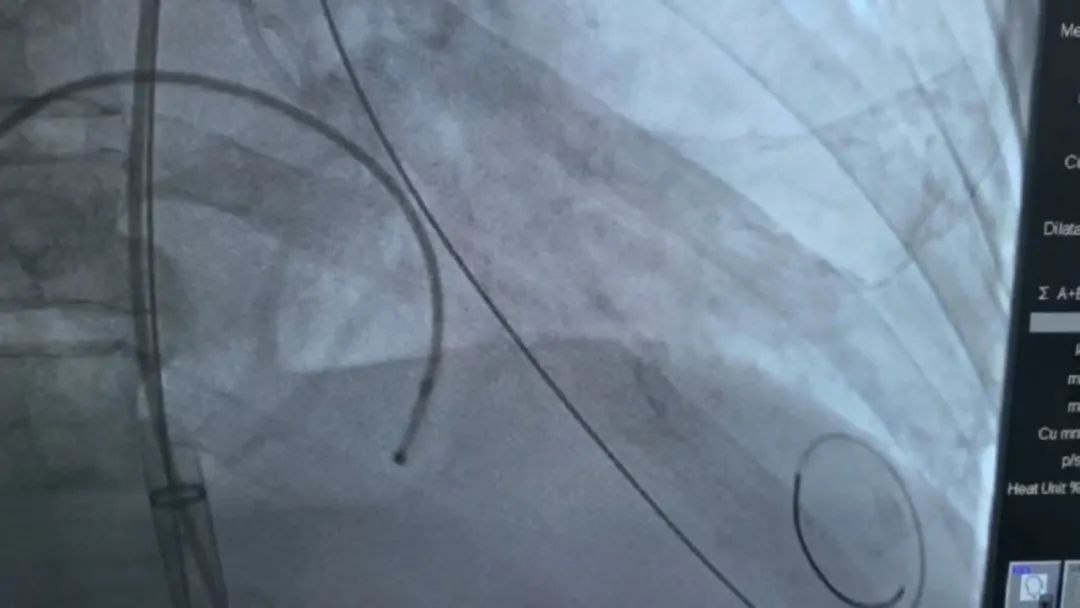

2月25日上午,上海市公共卫生临床中心心血管内科团队联合复旦大学附属中山医院心血管内科团队,成功为一名80岁高龄患者实施经导管主动脉瓣置换术(TAVR),在不开胸、心脏不停跳的情况下,为老人微创置换了心脏“大门”。

记者了解到,患者病情极为复杂且严重,其主动脉狭窄程度严重,还伴有大面积钙化,致使心脏压差急剧升高,心脏功能也因此受到极大损害。就在年前,患者突发急性肺水肿,情况危急。鉴于患者目前的身体状况,若采用传统手术方式,以他的身体机能和承受能力,无法耐受手术带来的创伤与风险。

为此,市公卫中心心血管内科徐亚伟教授、李宁荫主任团队依托多学科协作(MDT)模式,联合上海交通大学医学院附属同仁医院臧旺福心脏外科及体外循环团队,及中心胸外科、麻醉科、重症医学科、ECMO团队、放射科、介入科、超声科等科室专家,通过人工智能软件,精准评估病情,制定个性化TAVR手术方案,成功完成主动脉瓣膜置换,术后患者血流动力学显著改善,提高了患者的心脏功能和生活质量。

徐亚伟介绍,经导管主动脉瓣置换术是一种用于治疗主动脉瓣狭窄的创新型微创手术,可在心脏持续跳动的状态下,将人工瓣膜准确放置于病变瓣膜处,这也为许多高龄、身体状况差而无法耐受传统开胸手术的患者,提供了新的治疗希望。